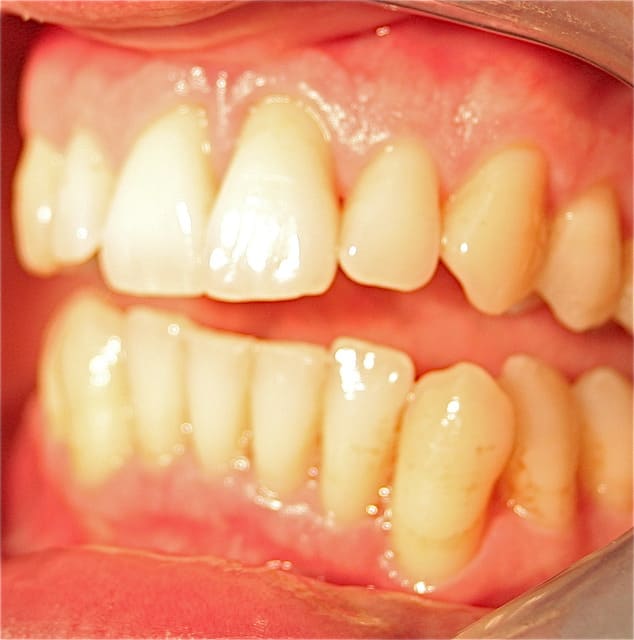

toujours aucune extractions depuis 8 ans, sur des cas de paro nommé irréparable par les plus grands parodontistes de France et de suisse! LOL

lus de 250 cas extrêmes et difficiles traités prouvent que nous sommes bien en présence d'une blessure souillée et qu'il suffit de la traiter comme toute blessure souillée.

donc ce qui me différencie de Jacques Charon et des aures , c'est que je ne parle plus en voyant le tableau clinique, saignements , gencive oedématiée, douleur, et gène fonctionnelle,(tous les signes d'une inflammation!), de "maladie" parodontale, mais bel et bien de "réparation" , cicatrisation, "voulue", dirigée et orchestrée, d'un point de vue biologique, car le corps n'a pas les moyens de se débarrasser des bactéries et autres corps étrangers, tartre notamment, installés sur la longueur de la racine, mais il a les moyens, et d'ailleurs l'article concernant l'inflammation, dans le numéro de Janvier de l'information dentaire, dossier "maladie parodontale" , le dit bien , que lors de l'inlammation, l'os est détruit! mais ce n'est pas une maladie, c'est un remède!

Les photos que tu montres ne donnent aucun renseignement quand à la guérison du parodonte (Ah oui , pardon ce n'est pas une maladie ).